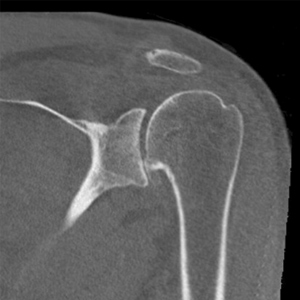

- Pyrocarbon hemiarthroplasty is a new option for patients (particularly younger, more active) with advanced arthritis

- Because a plastic socket is not placed into the socket, there is no risk of socket loosening with time

- While 10 year follow up from Europe demonstrates very low need for second surgery at 10 years (11%), an important factor is that the surgeon size the head correctly during surgery

Pyrocarbon shoulder hemiarthroplasty

- This is a case example of a patient in his 40s who presented to us with severe shoulder pain, inability to work out and even raise his shoulder to chest level! At 6 months postoperatively he is back to the activities that he wants, keeping him active and healthy again